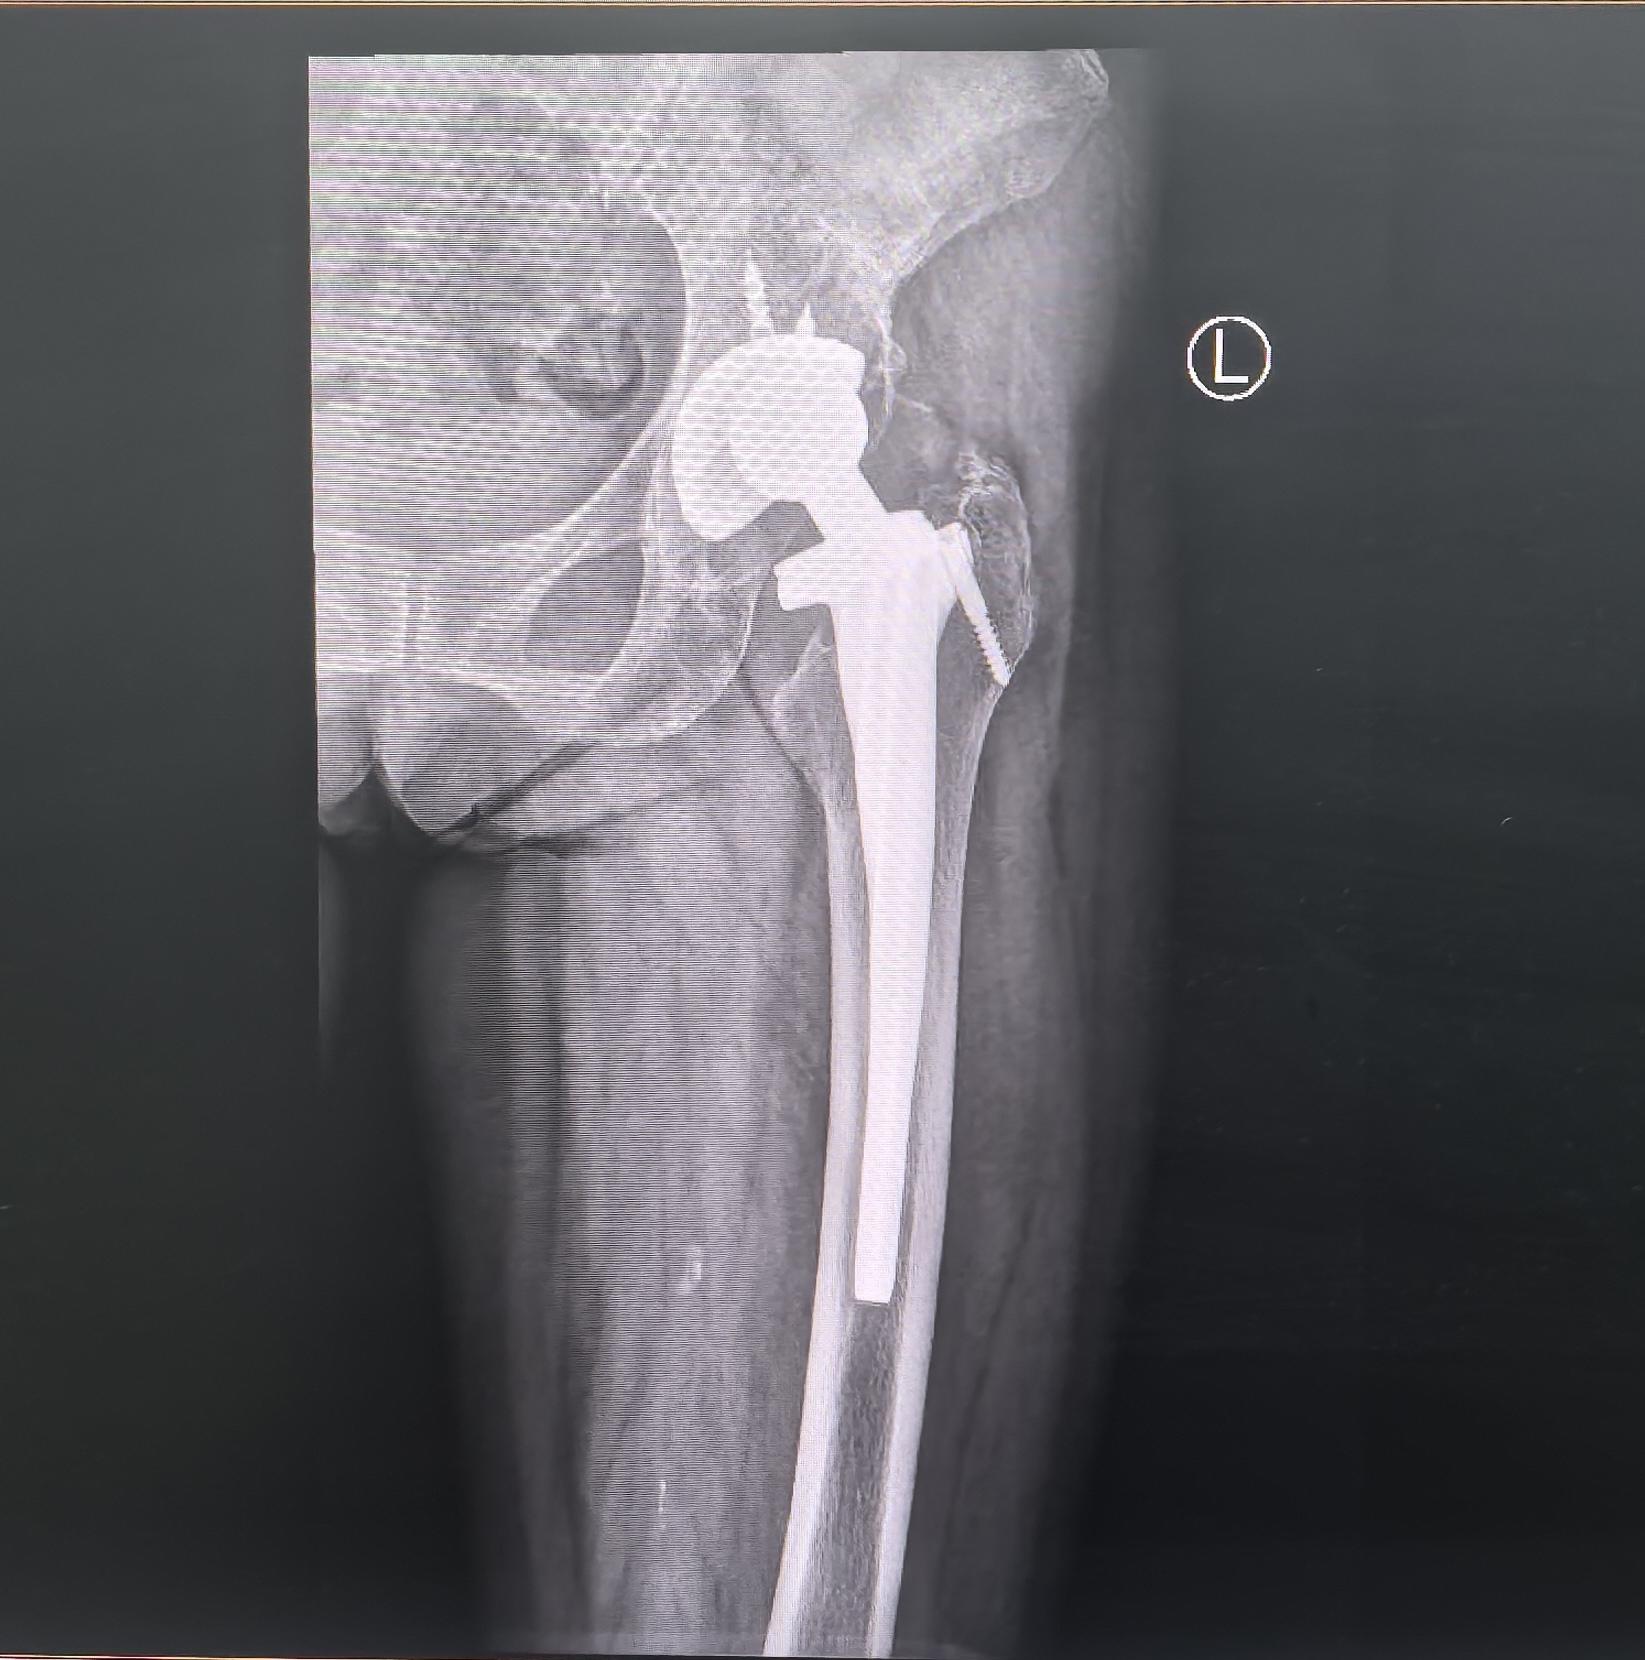

髋关节翻修。髋关节置换术后22年,假体磨损,骨溶解,无菌性松动,翻修术后再次恢复正常生活🌹